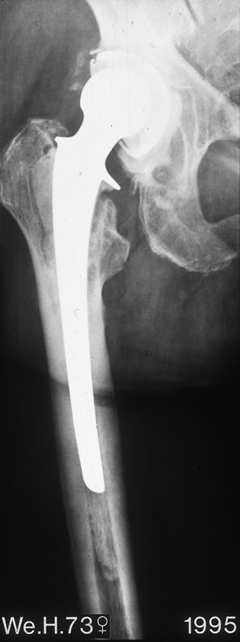

Fallbeispiel

Weiblich, 55 Jahre. Es zeigt sich eine schwere Dysplasiearthrose der

rechten Hüfte (links im Bild) sowie eine Subluxation des linken Hüftkopfes mit

partiellem Kopfeinbruch.

Beide

Hüftgelenke wurden in einer Operation ersetzt. Das Röntgen zeigt das

Ergebnis 10 Jahre postoperativ. Beide Hüften sind stabil im Knochen

verankert, die Patientin ist außerordentlich zufrieden.